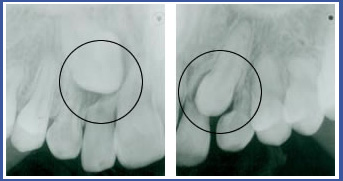

«Запертые» зубы

Существуют ситуации, когда зуб не может прорезаться в предназначенном для него месте на зубной дуге и остается «запертым» в десне.

Существует несколько основных причин для появления «запертых» зубов:

1.Зуб «запирается» вследствие тесноты, создавшейся на зубной дуге: свободное место, предназначающееся для прорезывания зуба, стало меньше, и ему негде прорезаться.

В таком случае зуб прорежется в неправильном месте или останется «запертым» в десне.

2. Перегораживание места для прорезывания: например, лишний зуб на данном участке или нерассосавшийся корень молочного зуба.

3. Неправильная траектория прорезывания. Постоянный зуб начинает развиваться в глубине десен и со временем прорезается. Зубы, у которых длинная траектория прорезывания, могут «ошибиться» и в результате останутся «запертыми» в деснах, в неправильном месте. Такие ситуации характерны для верхних клыков, у которых очень длинная траектория прорезывания (другие зубы тоже могут оказаться «запертыми», но реже). Частота появления «запертых» клыков у населения составляет 1%-3%